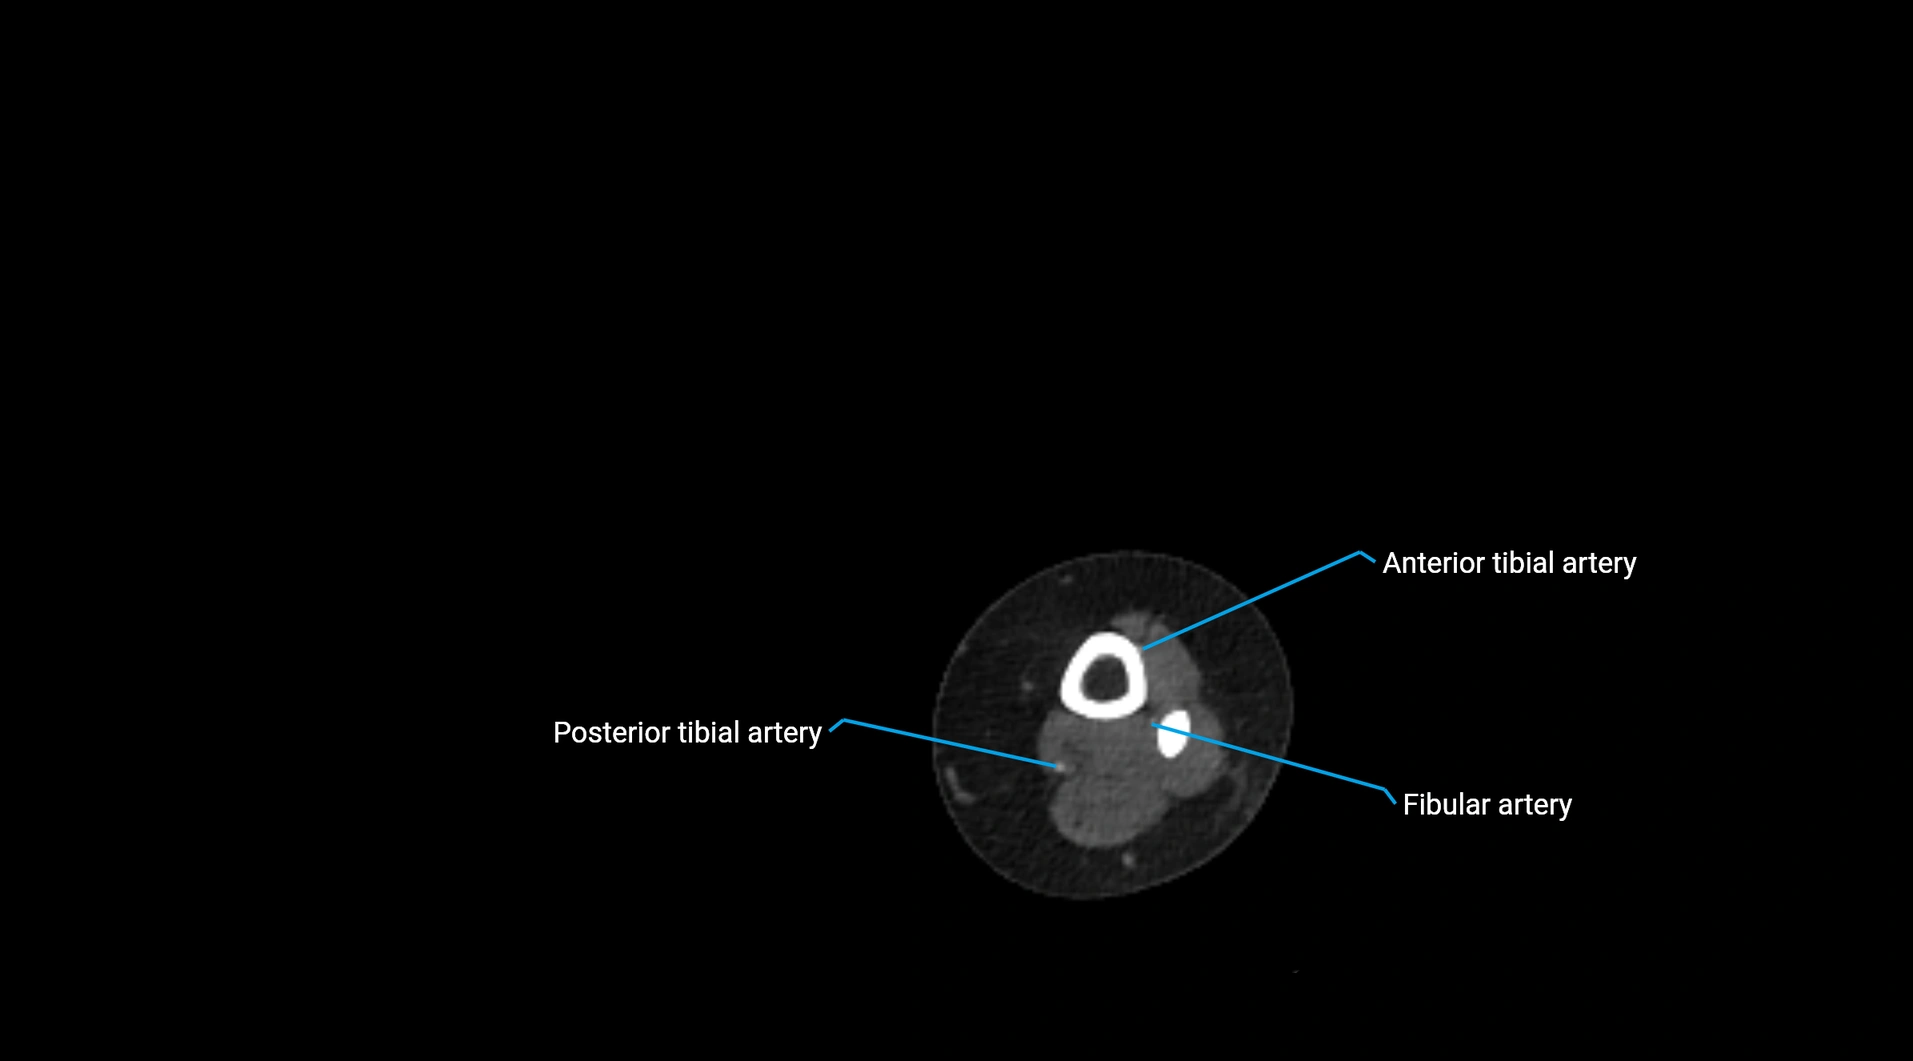

CT images

image